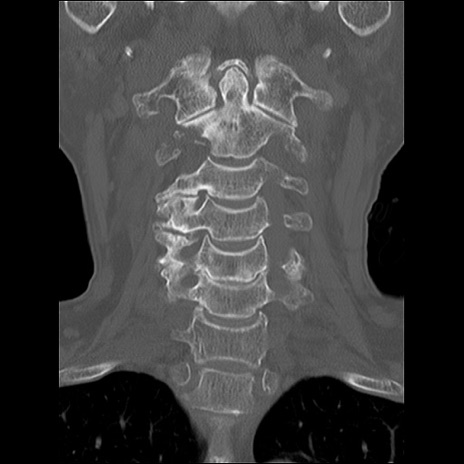

症例48 頚椎CT(冠状断像)

頚椎CT